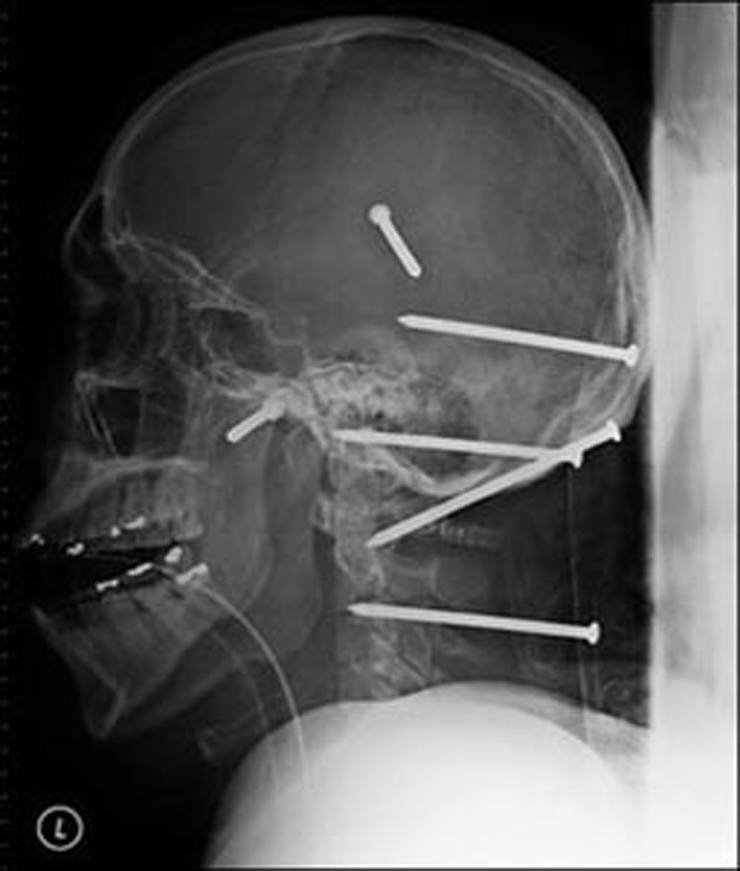

Сверло

18-дюймовое сверло пронзило глаз человека.